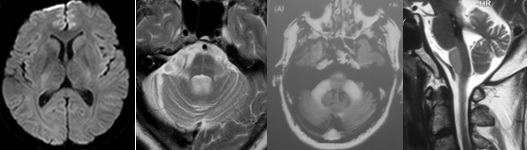

重要申明:以下每个部分会配磁共振图片,因疾病和影像之间存在同病异象、同像异病,为避免误导,图片不标注疾病,请各自鉴赏,另其中有部分图片来源于网络,有疑问可与本人联系。

H--hereditary,遗传

引起中枢神经系统病变的遗传性疾病可是种类繁多,主要指脑白质营养不良、脑小血管病等白质受累为主的病变。

如前者按发病机制可分为:溶酶体疾病(异染性脑白质营养不良、Fabry’s 病、Krabbe’s 病),过氧化物酶疾病(肾上腺脑白质营养不良(ALD)、肾上腺脊髓神经病(Adrenomyeloneuropathy))、线粒体疾病(MELAS、Leigh病)。按髓鞘病变病理过程种类分:异常髓鞘化:肾上腺脑白质营养不良、球形细胞脑白质营养不良、 染性脑白质营养不良;髓鞘化低下:佩梅氏病、Alexander病、白质消融性脑白质病;髓鞘囊性变性:Canavan病、空泡性脑白质病。

各种遗传性脑小血管病:如CADASIL、CARASIL、Fabry病及CAA、CAA相关性血管炎等等。

还有结节性硬化、各类NBIA(脑组织铁沉积神经变性病),脑肝肾综合征、线粒体脑病、LCC等。